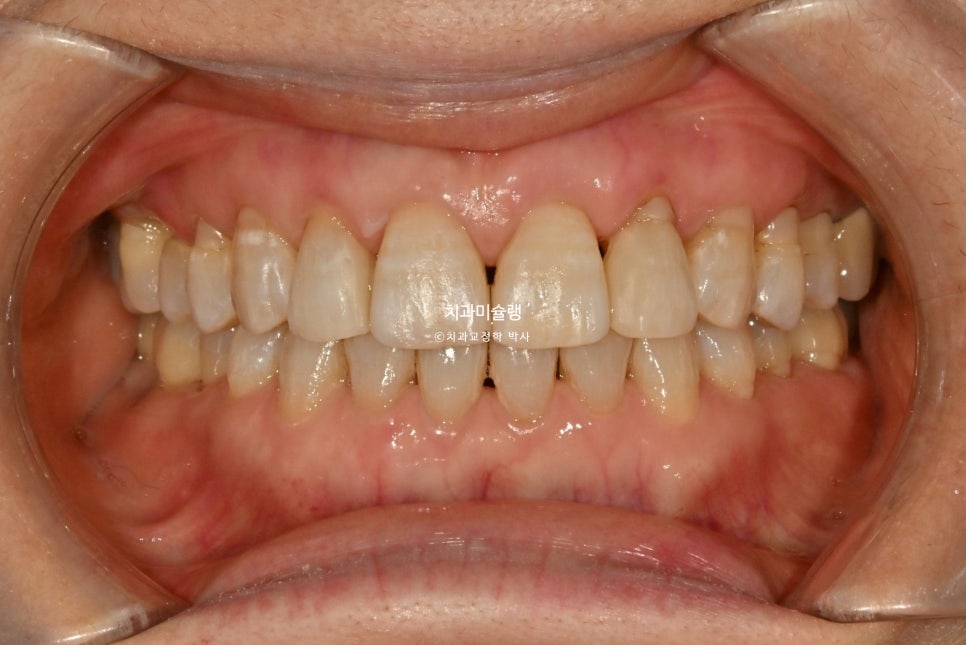

2025년 2월, 치료를 마무리 했습니다.

총 치료기간은 11개월입니다.

어금니 교합은 그대로 유지되었으며 돌출되고 벌어진 앞니는 깔끔하게 제자리를 찾았습니다.

앞니 부분교정이지만 한결 깔끔해진 미소가 돋보입니다.

100세시대의 60대면 이제 막 중간분기점을 돌아나온 시점인데, 치열과 미소를 건강하게 정돈해 놓는 치료는 무엇보다 가치있는 치료라고 생각합니다.

튀어나오고 솟아내려온 앞니가 들어가며

입술 다무는게 조금 편해졌다고 하십니다.